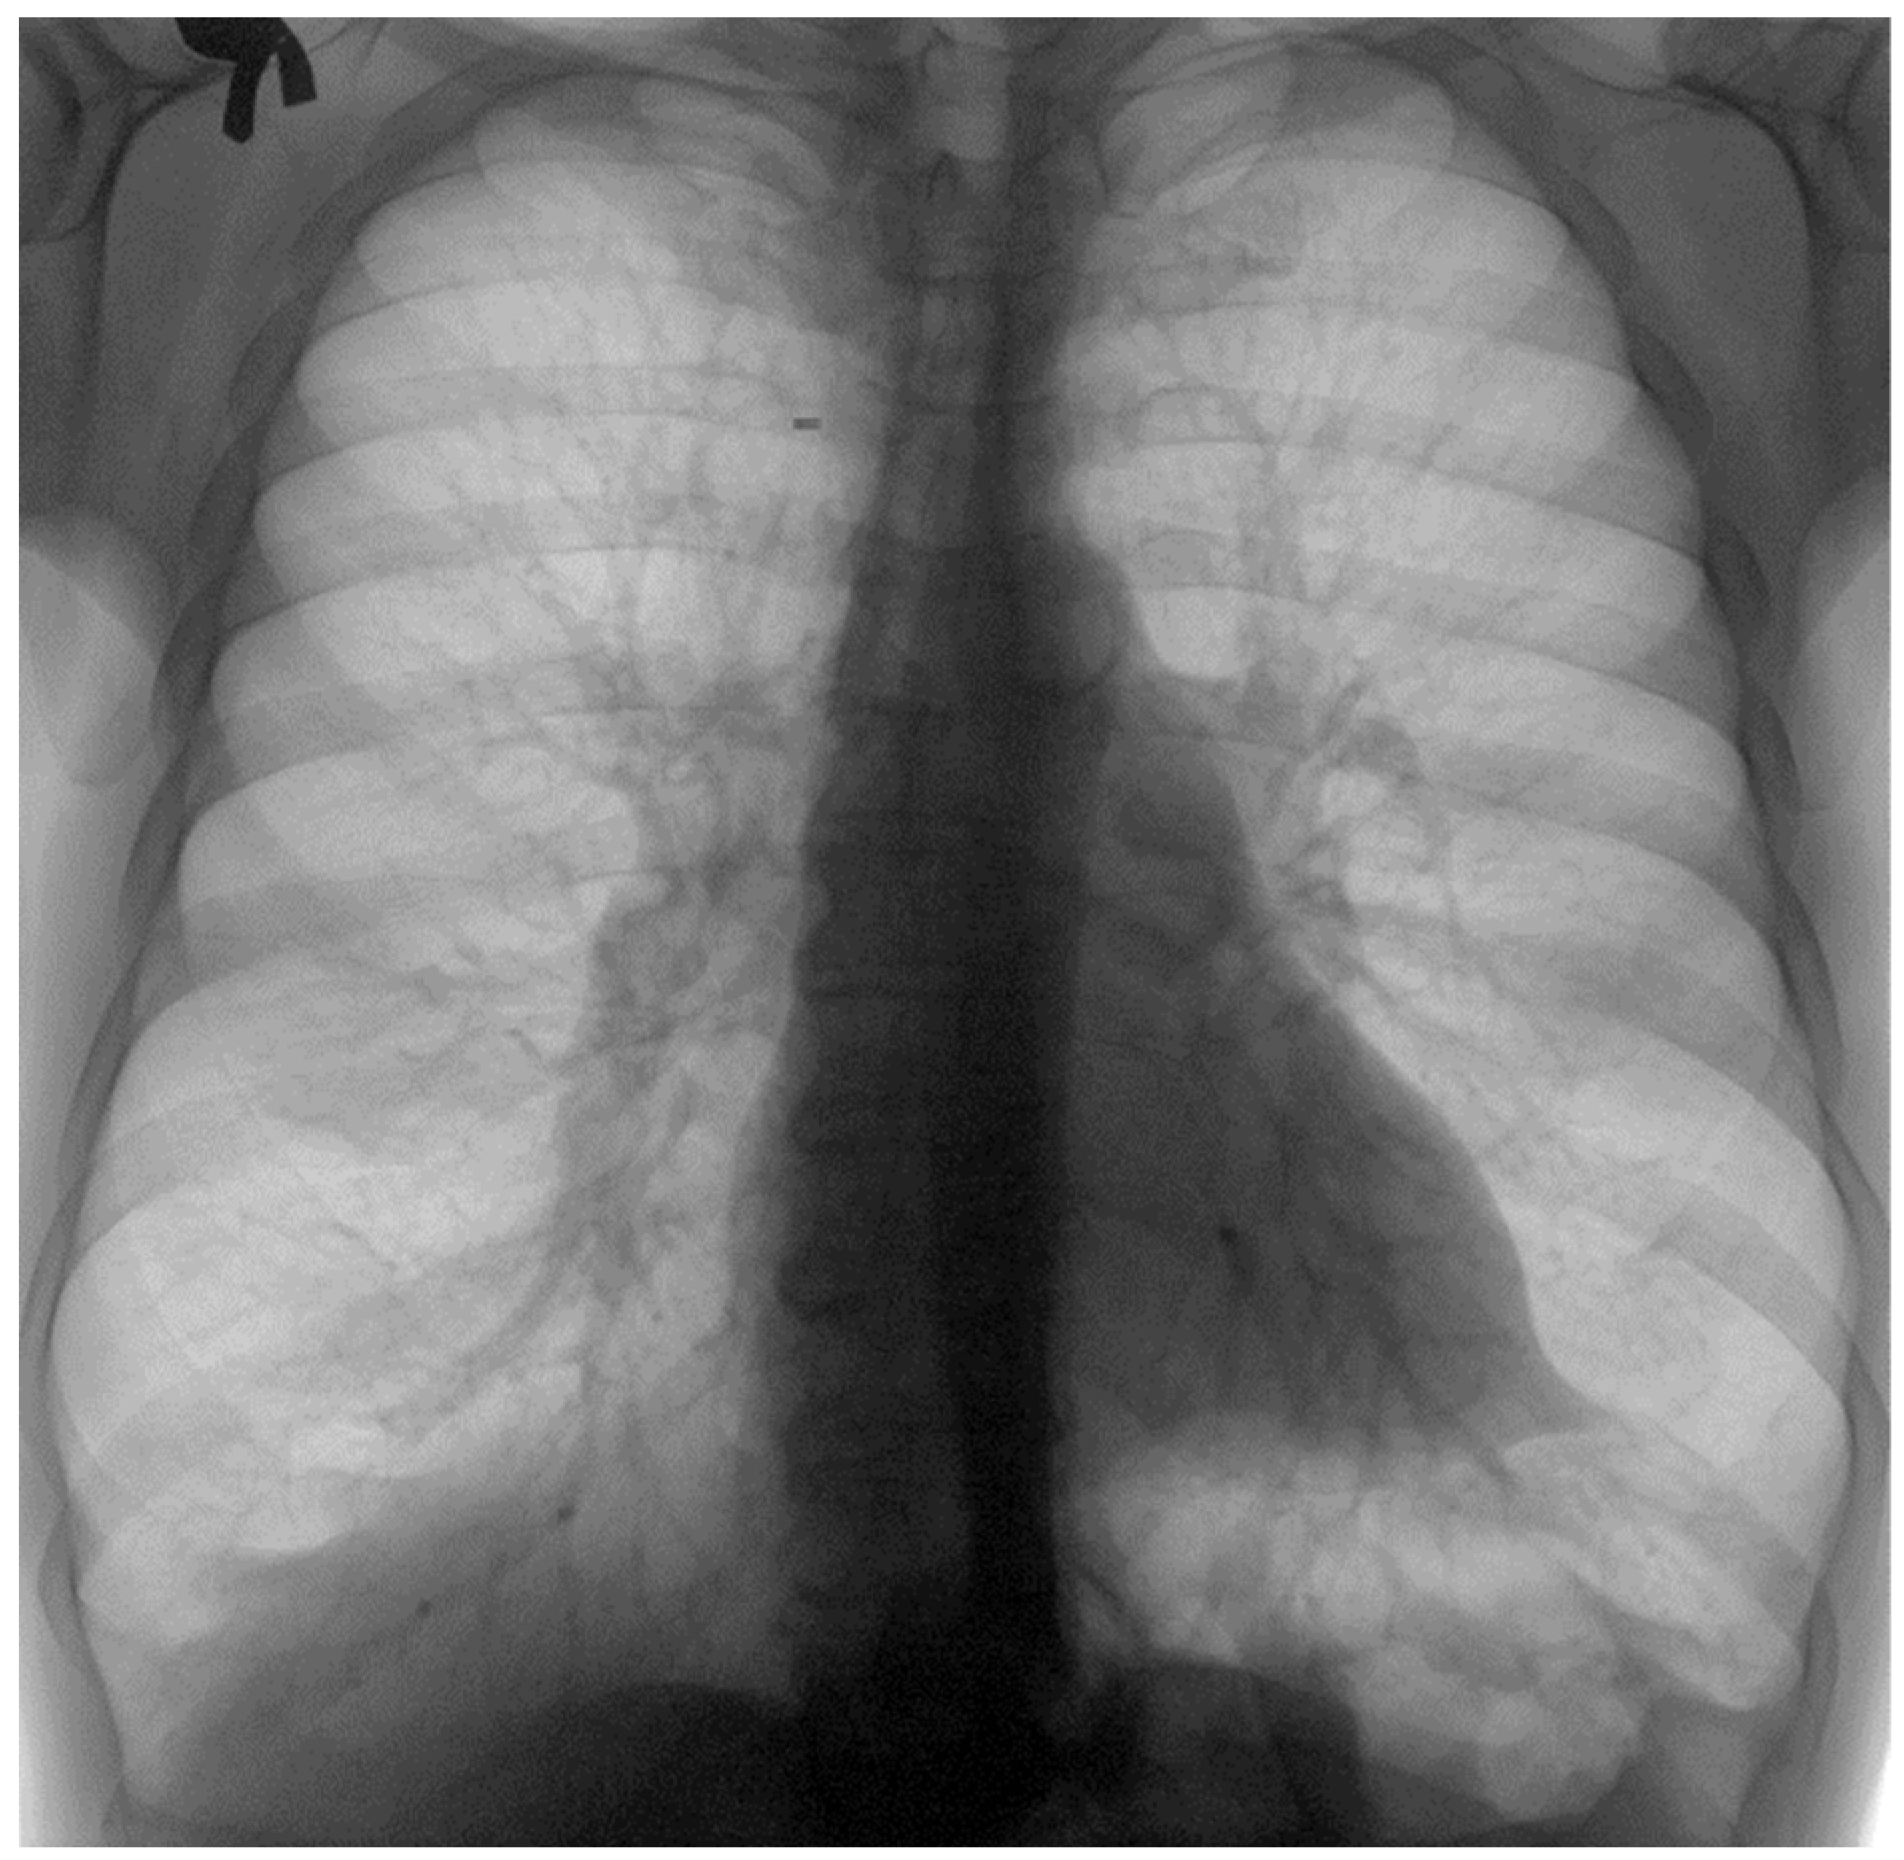

3.7. Results of Healthy Patients—A Final Comparison Using Control Data

In this subsection, we present and discuss the pulmonary CT scan of healthy lungs, which were not affected by the presence of SARS-CoV-2.

The chest radiograph of healthy lungs on which the fractal analysis was performed is shown in Figure 29a. Aside from the high-quality imaging provided by CT procedures (Figure 29a,b), the picture evaluation assured quantitative information regarding various structural features, such as the fractal dimension and lacunarity.

Figure 30 shows the 2D box-counting algorithm with the local fractal dimension calculation for the healthy-lung CT image. Figure 31 displays the 3D graphical representation of the voxels present in the CT lung image of healthy patient. Table 7 presents the calculated values for the fractal dimension and the lacunarity of the CT image evaluations for the healthy patient.

Table 7 shows the known fractal indicators, such as the fractal dimension of the CT image of the left lung, dHL = 1.6410 ± 0.3577, and lacunarity Λ = 0.0475; and the fractal dimension of the right lung, dHR = 1.6318 ± 0.3598, and lacunarity, Λ = 0.0486.